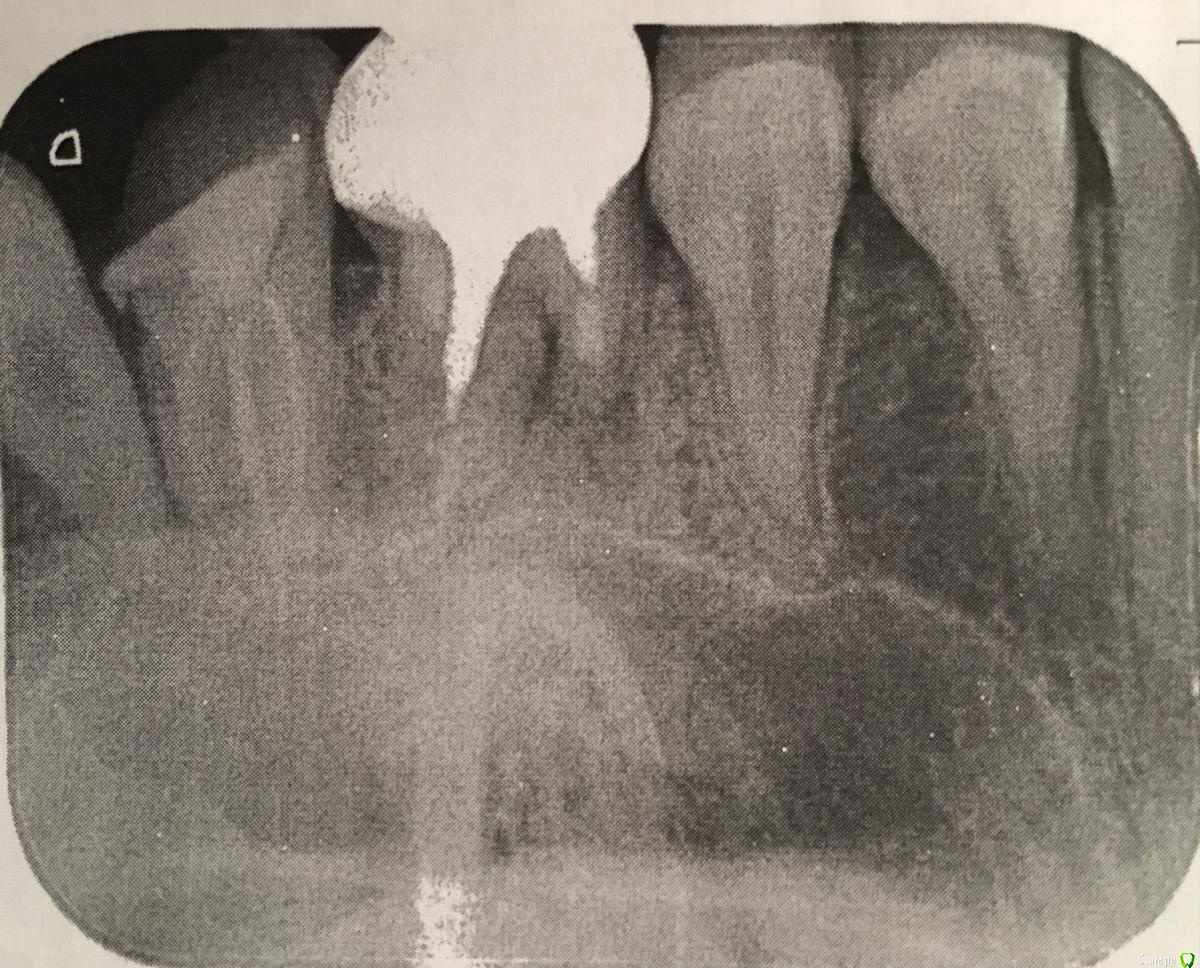

Barbusenok Опубликовано 11 ноября, 2017 Поделиться Опубликовано 11 ноября, 2017 (изменено) Здравствуйте уважаемые специалисты!Наверняка подобные вопросы уже задавались, но если возможно, прокомментируйте мой случай. Итак, беременность, 23 недели. 2 дня назад начал сильно болеть зуб (его лечили когда то очень давно, делали ли резекцию именно этого зуба уже не помню).Доктор при надавливании "снаружи" обнаружил локацию боли над зудом. Сделал снимок и на его основании сказал, что шансов на собрание зуба никаких нет и нужно удалять. Если не сложно, выскажите пожалуйста своё мнение, действительно ли нет никаких шансов сохранить зуб (например, попробовать дотерпеть до родов и начинать лечение)?Заранее спасибо! Изменено 11 ноября, 2017 пользователем Barbusenok Ссылка на комментарий

red_butler Опубликовано 11 ноября, 2017 Поделиться Опубликовано 11 ноября, 2017 снимок плохого качества, если зуб «дорог» снимать коронку и оценивать объем оставшихся тканей, после этого принимать решение. Но оставлять на самотек не стоит. 1 Ссылка на комментарий